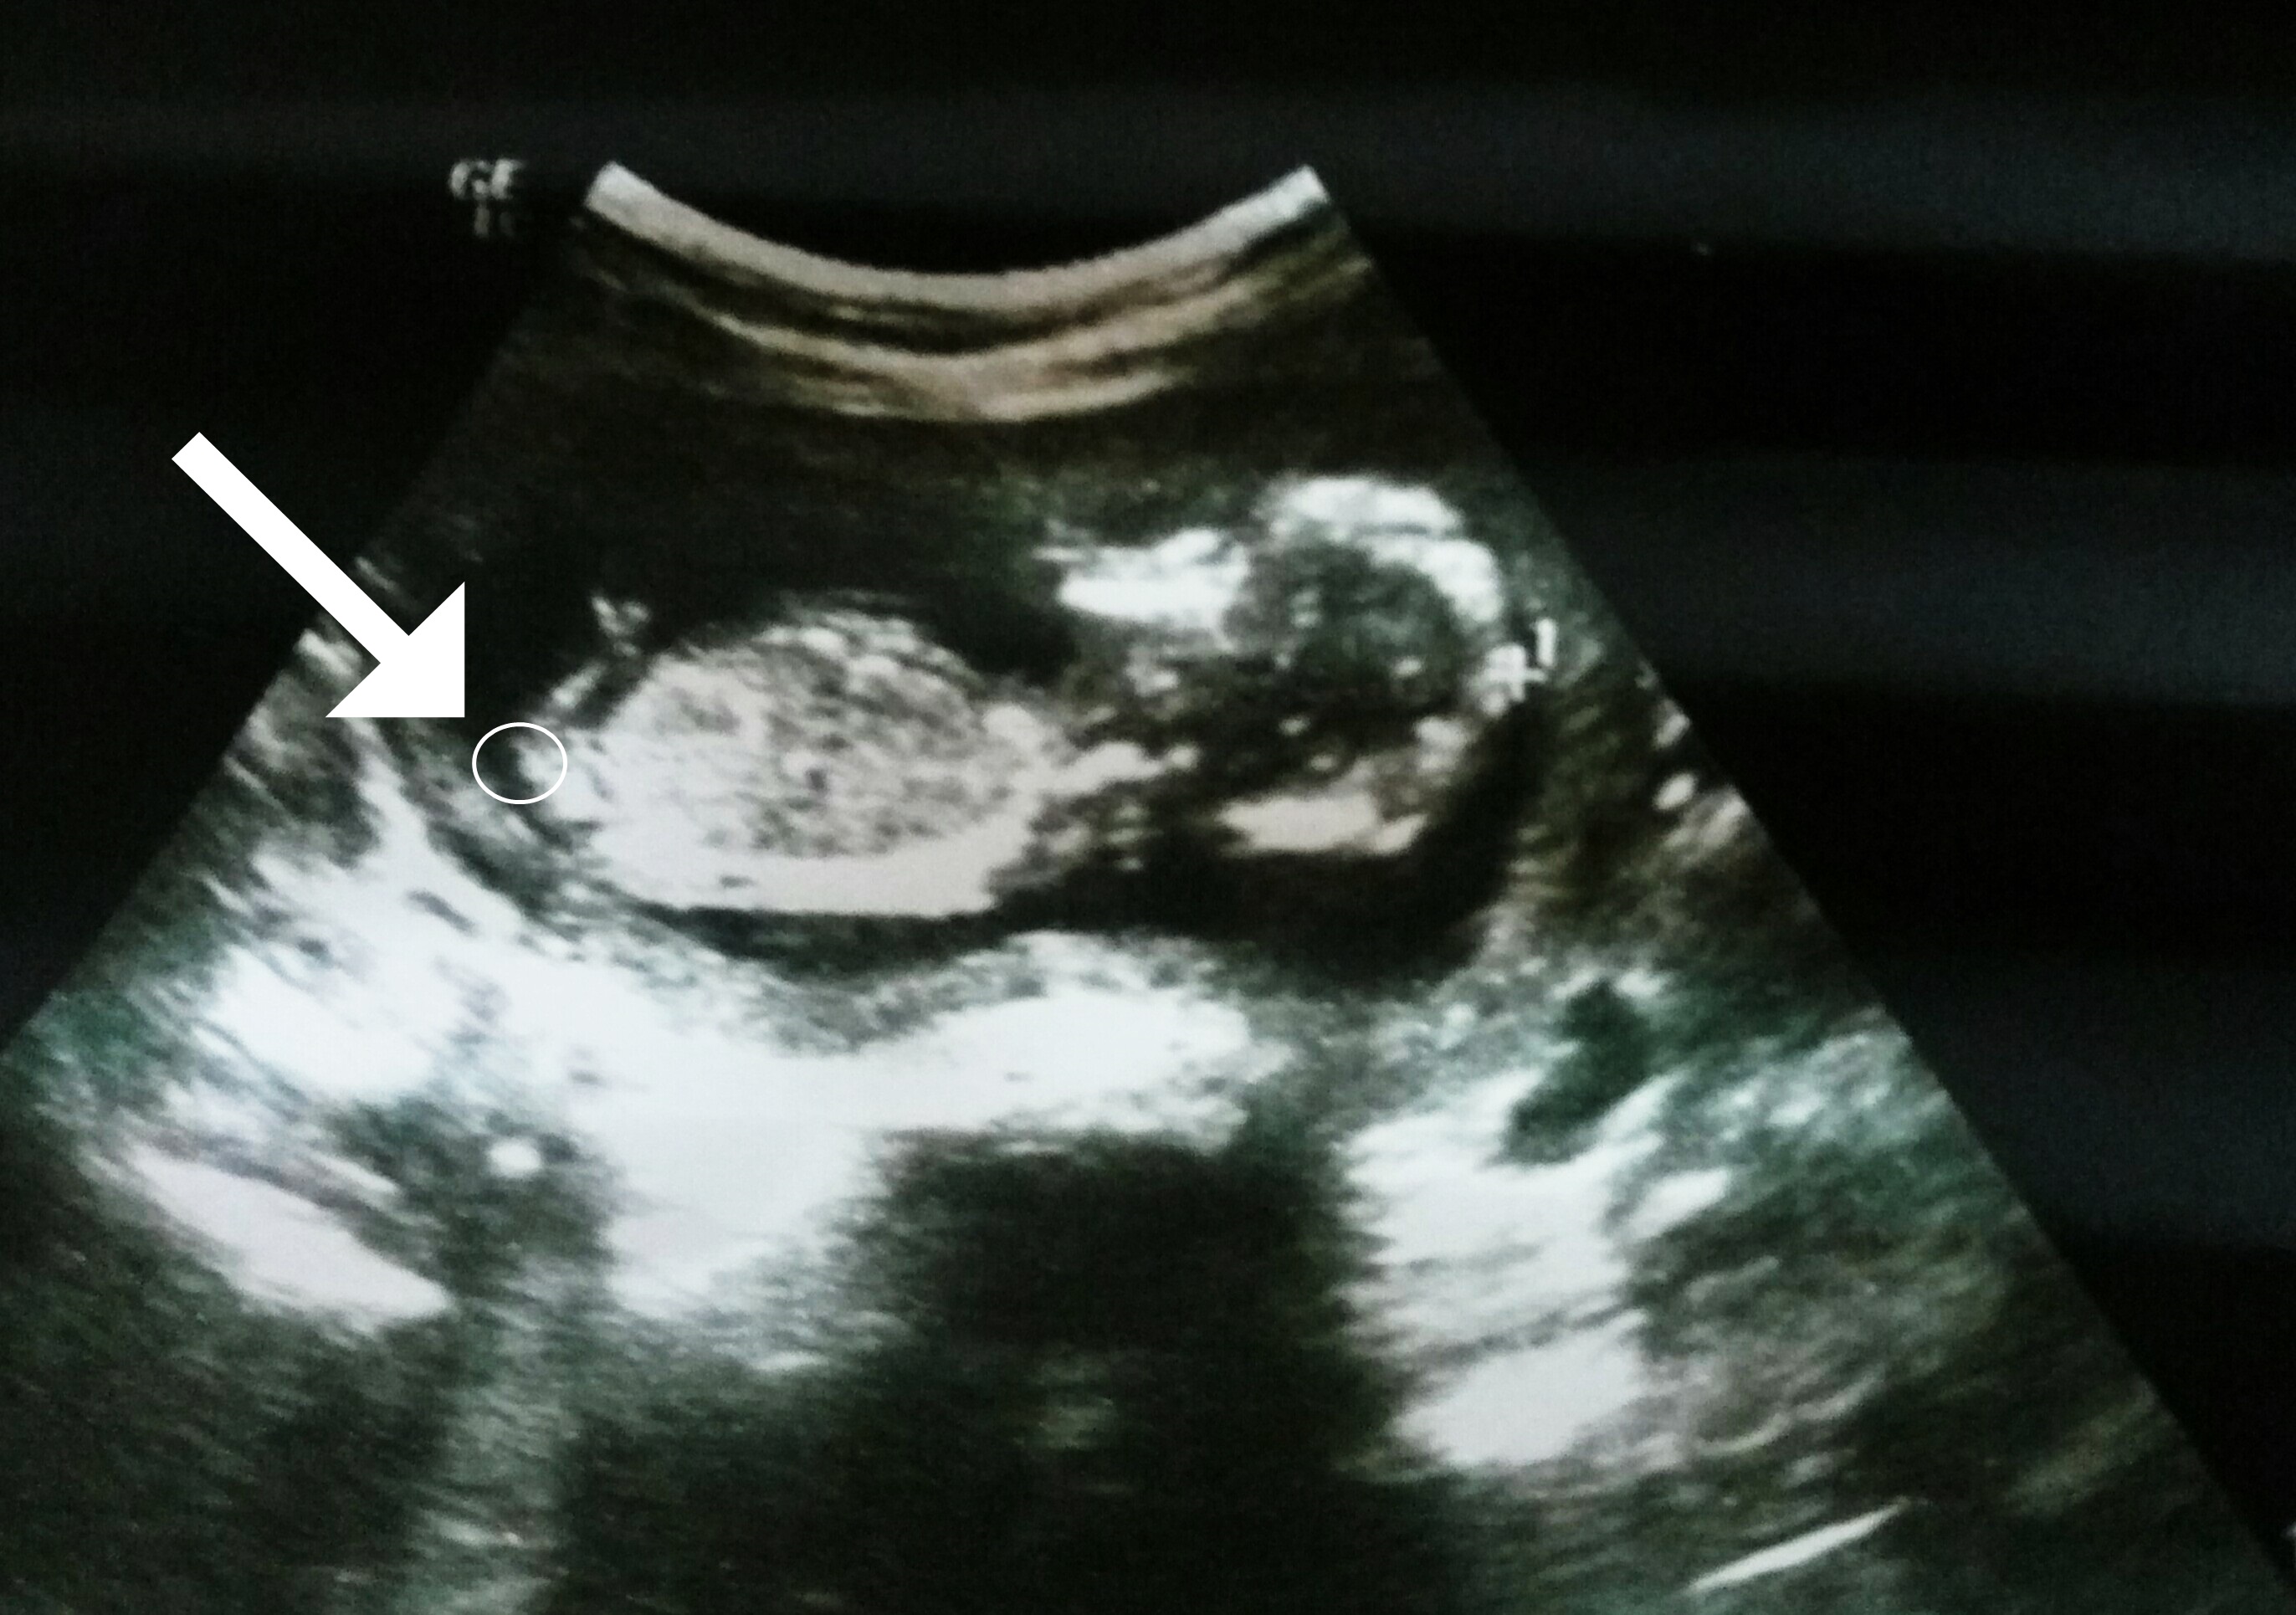

11+2 yorum yapmıştınız doktorum 14 haftada yine söylemedi resim de 14+4 haftalık suan 17 haftalığım bi doktor kesin değil erkeğe benziyor dedi 16 haftafa diğeri de tam göremiyorum kız gibi dedi sizce ne cevap lütfen

11+2 yorum yapmıştınız doktorum 14 haftada yine söylemedi resim de 14+4 haftalık suan 17 haftalığım bi doktor kesin değil erkeğe benziyor dedi 16 haftafa diğeri de tam göremiyorum kız gibi dedi sizce ne cevap lütfen Ekli dosyayı görüntüle 72508